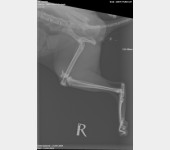

Jest szansa na uratowanie Bajki, ma złamaną prawą tylną łapką i pogruchotaną w kilku miejscach miednicę. Niestety - nasze możliwości finansowe się wyczerpały, życie dość mocno sie ze mną obeszło w ostatnich latach i nie mam generalnie nic. Dziś wydaliśmy wszystkie skromne oszczędności, żeby opłacić leczenie Bajki do tej pory.

Kochani, dzięki Waszym wielkim sercom Bajka dziś pomyślnie przeszła operację - DZIĘKUJEMY ????♥️???? Wielkie brawa dla lekarzy z lecznicy Cztery Łapy w Jeleniej Górze ! Koszt operacji wyniósł 3260 PLN plus każdorazowa wizyta kontrolna 30 PLN plus koszty dodatkowe za miesiąc, tj. wyjęcie śrub, leki, rehabilitacja. Dziś zapłaciłem 3000 PLN, załączam rachunek. Następne załączę przy kolejnych opłatach. Bajka wysyła miaubuźki (. ❛ ᴗ ❛.)